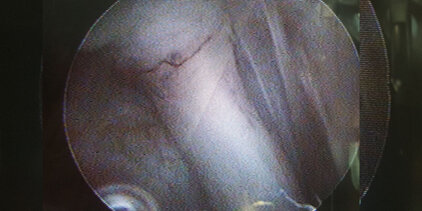

Arthrotomie/Arthroskopie

Minimal Invasive Diagnostik und Behandlung von Gelenkserkrankungen der großen Gelenke Schulter, Ellenbogen und Knie. Insbesondere Knorpel- und Knochenschäden in Schulter und Ellenbogen (OCD Osteochondrosis dissecans, FPC Frakturierter Processus coronoideus, IPA Isolierter Processus anconaeus), chronische Sehnenentzündungen der Bicepssehne im Schultergelenk und Band-/Meniskusverletzungen im Kniegelenk.